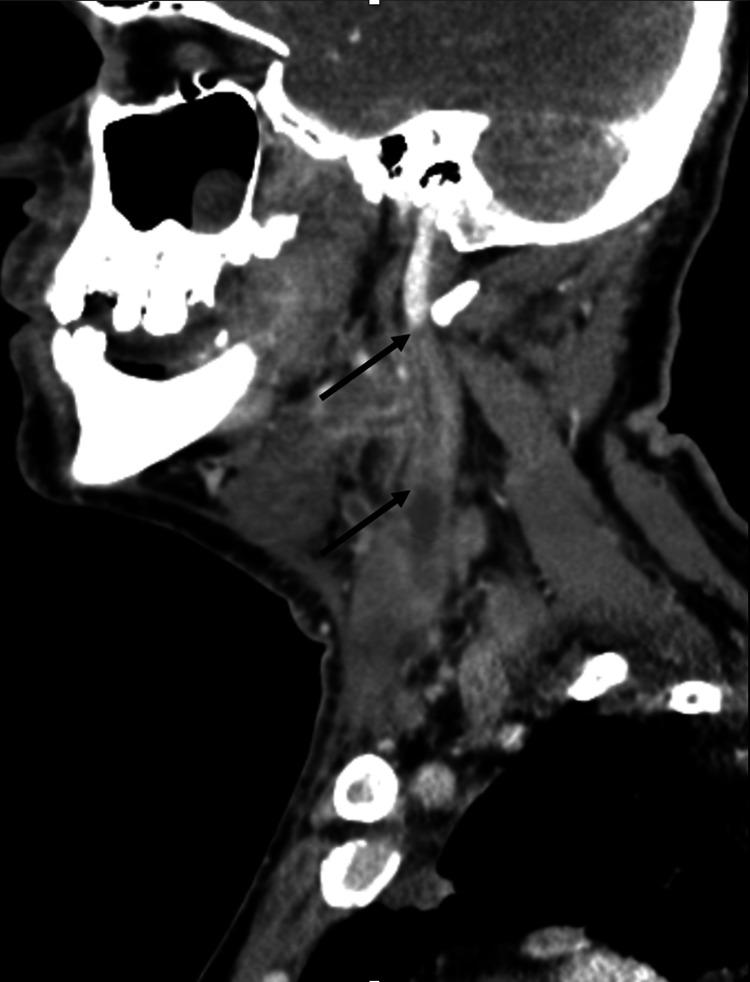

Lemierre's syndrome is a rare and potentially life-threatening complication of head and neck infections, such as bacterial pharyngitis or tonsillitis. It is characterized by the extension of infection into the lateral pharyngeal spaces, leading to subsequent septic thrombophlebitis of the internal jugular vein(s). Although relatively uncommon since the advent of appropriate antibiotic therapy, the incidence of Lemierre's syndrome has increased in the past 15 years, especially among young, healthy adults. This increase is likely attributed to the increasing prevalence of oropharyngeal infections in this population, making an initial diagnosis of Lemierre's syndrome often elusive on presentation. Delayed recognition of this syndrome can result in treatment delays, increasing the morbidity and mortality in this condition. The diagnosis of Lemierre's syndrome is typically confirmed through the identification of thrombophlebitis of the internal jugular vein on radiographic imaging and the isolation of anaerobic bacteria in blood cultures. Treatment involves prolonged antibiotic therapy and, often, anticoagulation. This case report presents a rare complication of bacterial tonsillitis, with initial imaging that demonstrated left peritonsillar phlegmon and subtle micro-occlusions of the left internal jugular vein on early imaging. Within four days, the infection rapidly progressed to complete occlusion of the internal jugular vein with pulmonary septic emboli, culminating in Lemierre's syndrome. This case highlights the importance of early detection and treatment of subtle radiographic findings of thromboses, along with consideration of social determinants of health, in the setting of head and neck infections to avoid rapid progression to Lemierre's syndrome, a disease with an elusive initial presentation and potentially fatal outcomes.

勒米尔综合征是头颈部感染(如细菌性咽炎或扁桃体炎)的一种罕见且可能危及生命的并发症。其特征是感染蔓延至咽旁间隙,继而导致颈内静脉脓毒性血栓性静脉炎。自适当抗生素疗法问世以来,虽然相对不常见,但勒米尔综合征的发病率在过去15年中有所上升,尤其是在年轻健康的成年人中。这种上升可能归因于该人群口咽感染患病率的增加,使得勒米尔综合征在初诊时常常难以确诊。对该综合征的延迟识别可能导致治疗延误,增加该病的发病率和死亡率。勒米尔综合征的诊断通常通过影像学检查发现颈内静脉血栓性静脉炎以及血培养中分离出厌氧菌来确诊。治疗包括长期抗生素治疗,通常还需要抗凝治疗。本病例报告呈现了一例细菌性扁桃体炎的罕见并发症,早期影像学显示左侧扁桃体周围蜂窝织炎以及左侧颈内静脉细微的微血栓形成。在四天内,感染迅速进展为颈内静脉完全闭塞并伴有肺脓毒性栓子,最终发展为勒米尔综合征。该病例强调了在头颈部感染的情况下,早期发现和治疗血栓形成的细微影像学表现的重要性,并考虑健康的社会决定因素,以避免迅速发展为勒米尔综合征,该病初发表现隐匿且可能导致致命后果。